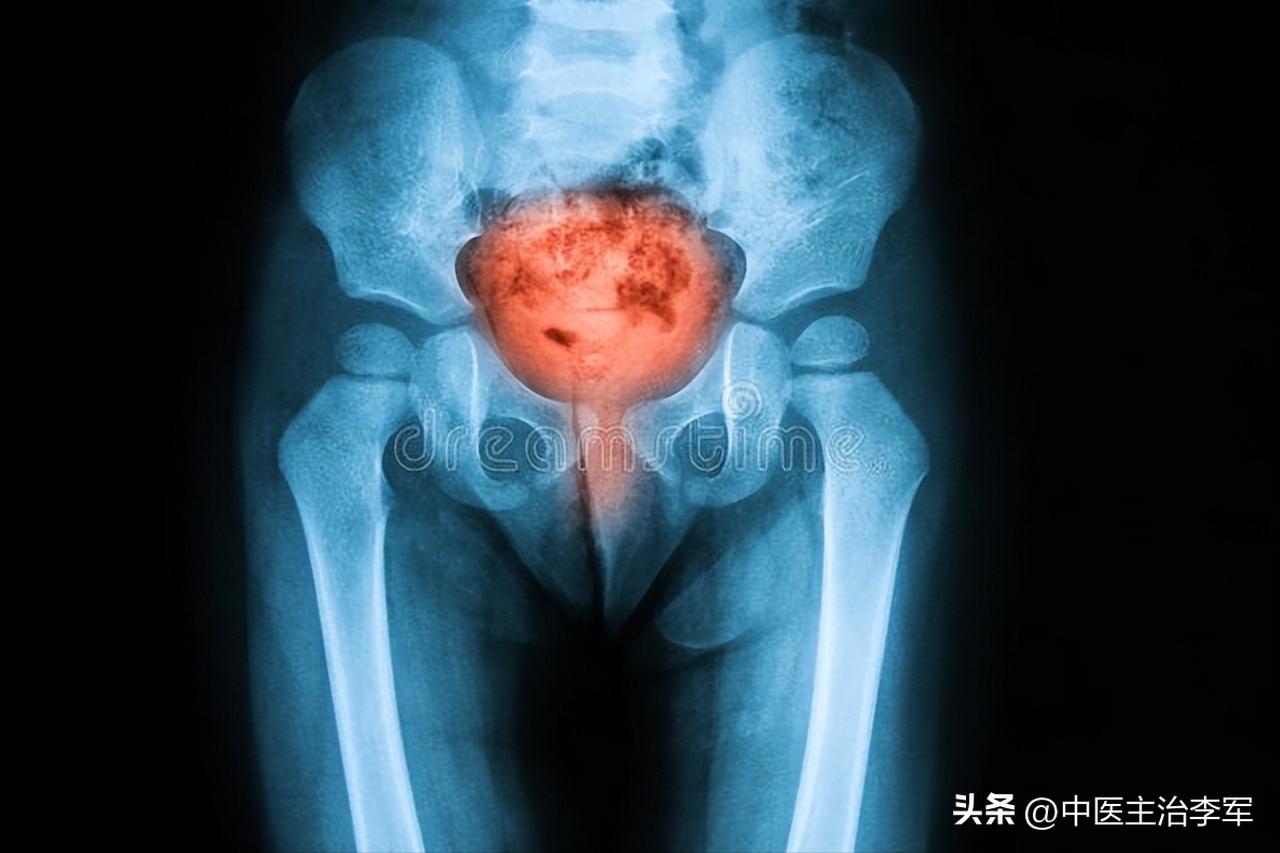

第三个:膀胱炎

症状:小便色黄或淡红,尿量少,尿道口发红发痒,尿的时候出现刺痛感

辩证:肝胆实火下移到膀胱,导致膀胱出现湿热,然后出现泌尿系统的发炎。

如何调理:清泄膀胱积热